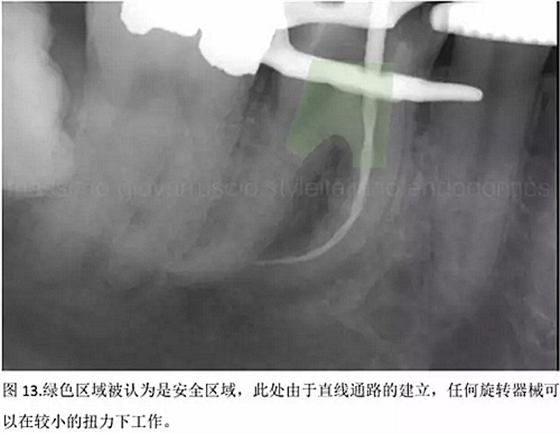

開髓后預(yù)敞、探查根管、建立直線通路是根管機(jī)械預(yù)備的第一步。在這些階段中,醫(yī)生可能會(huì)經(jīng)常遇到一些困難。這些難題包括器械折斷、臺(tái)階形成、根管歧坡或根管拉直、帶狀穿孔、根尖穿孔、根尖肘形、根尖堵塞。所有這些錯(cuò)誤可導(dǎo)致根管系統(tǒng)清潔不完善從而降低牙髓治療成功率。

結(jié)論:本文的目的是描述一種旨在優(yōu)化根管根尖部分預(yù)備的預(yù)敞技術(shù)。根管頸部或冠方的早期預(yù)敞對(duì)于減少初尖銼直徑和根尖部根管直徑之間的差異至關(guān)重要。大量研究表明,手用或機(jī)用器械預(yù)敞根管能顯著減少器械折斷的發(fā)生率。下一篇文章將描述如何建立可重復(fù)的引導(dǎo)路徑。而引導(dǎo)路徑是指鎳鈦器械可沿著光滑根管壁輕易地滑行至工作長(zhǎng)度的通路。